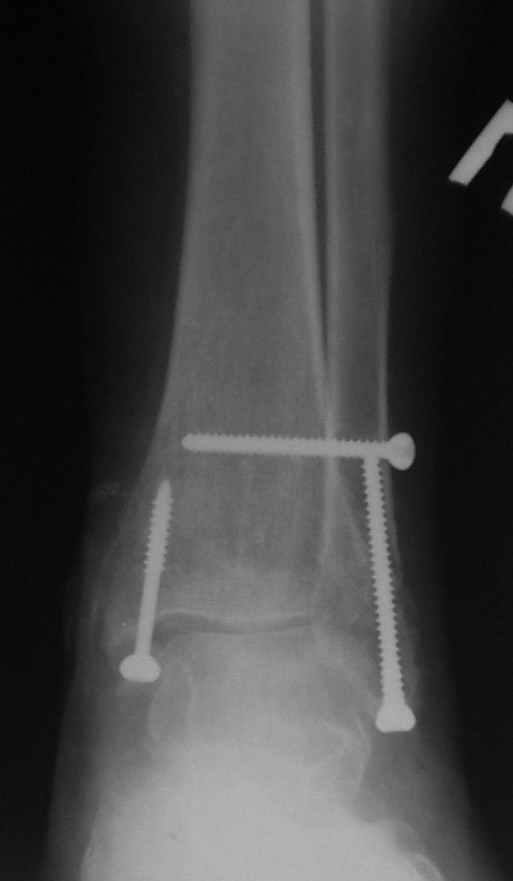

15 ноября прямой